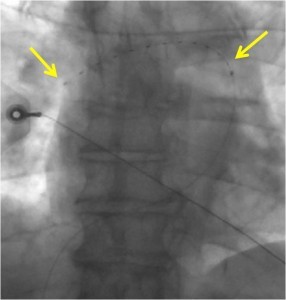

EKOS TM catheter seated in the right main pulmonary artery via the right femoral vein. The catheter segment between the yellow areas is the” treatment zone”, where thrombolytic agent is administered and ultrasound energy is emitted. The combined slow elution of TPA coupled with ultrasound energy is thought to accelerate thrombolysis by allowing deeper penetration of TPA into thrombus (Owens, Sem Interv Radiol 2008). To our knowledge, there are no published randomized data showing superior, non-surrogate clinical outcomes with EKOS compared to traditional infusion catheters. The ULTIMA trial first published after the 2013 ACC conference in San Fransisco was a randomized comparison of the EKOS catheter and anticoagulation for 59 patients with submassive pulmonary emboli. The study showed better 24 hour right ventricular size with the advanced therapy.